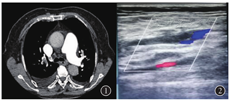

忠者女,75岁,主因间断右上腹胀痛伴恶心1个月余就诊。既往慢性支气管炎20余年,双下肢静脉曲张10余年。査体:脉搏105次/min,呼吸频率24次/min。双肺呼吸音弱,未闻及干湿性啰音,心律齐,各瓣膜听诊区未闻及杂音,腹平软,右上腹压痛阳性,无反跳痛,Murphy征阴性,未触及包块,双下肢无明显肿胀。急诊行腹部彩超:肝右叶单发囊肿,慢性胆囊炎。遂以"慢性胆囊炎急性发作"收住入院。入院后给予禁饮食、补液、抗感染等治疗,腹痛症状无明显缓解。期间血常规:WBC 4.8 × 109/L,中性粒细胞63.4%;动脉血气分析:PO2 48.9 mmHg,PCO2 36.3 mmHg。凝血系列: D-D 3 175 ng/ml,FIB 1.53 g/L。胸部CT:右肺上叶后段及下叶炎性病变,右侧胸腔积液,双侧胸膜增厚。心脏增大,心包增厚,肺动脉增宽。心脏彩超:右房、右室扩大,三尖瓣关闭不全(轻-中度),PAP 49 mmHg。追问病史,患者诉右小腿曾感憋胀不适。胸部CTPA示:双肺多发肺动脉栓塞(图1);肺动脉高压,右侧胸腔积液,右肺下叶膨胀不全,下肢静脉彩超:右侧小隐静脉血栓形成,双小腿肌间静脉、穿静脉血栓形成(图2)。确诊为肺栓塞,给予抗凝(低分子肝素)、活血等治疗,患者腹痛较前明显好转并出院,院外规律口服华法林抗凝治疗,无下肢肿胀、胸憋、气紧等症状。